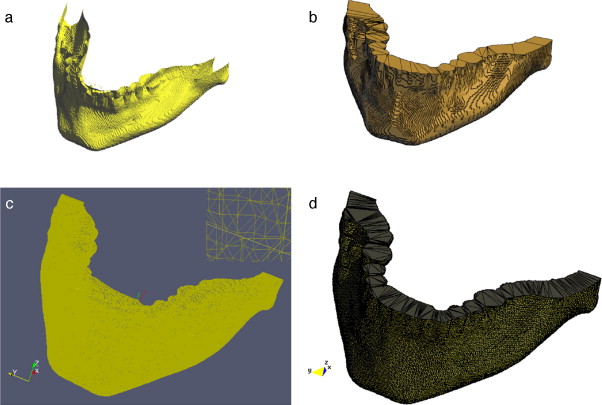

3.4. Modelado del hueso cráneo-facial

En imágenes de TC, las estructuras óseas son representadas con niveles de gris más altos comparado con los otros tipos de tejidos presentes en estas imágenes, debido a esta característica resulta útil aplicar técnicas de umbralización para separar este tipo de tejidos óseos de los demás. Sin embargo, el uso de umbralización puede tener la desventaja de generar pequeñas zonas desconectadas dentro de la misma estructura o fuera de ésta y a la vez generar zonas superpuestas en las superficies de los huesos, por los cuales se hace necesario aplicar técnicas de filtrado y suavizado de ruido antes de segmentar, así como realizar un remuestreo de los modelos segmentados aplicando técnicas de dilatación morfológica para rellenar los agujeros presentes y suavizar capas externas de los modelos óseos.

Para verificar la correcta combinación de estas técnicas y su utilidad, éstas fueron aplicadas en imágenes de TC del cerebro para obtener el modelo geométrico del hueso cráneo-facial, el flujograma de algoritmos utilizado es presentado en la figura 21 . Cada proceso es descrito a continuación.

3.4.1. Preproceso

Para la reducción del ruido de las imágenes de TC se aplicó el filtro de difusión anisotrópica, asimismo, se consiguió uniformizar los niveles de gris de los tejidos en la imagen.

3.4.2. Segmentación

Para segmentar el hueso del cráneo se utilizó la técnica de umbralización. Se observó el histograma global de la imagen y se seleccionó un valor umbral que separara el tejido óseo de los demás tejidos, obteniéndose una imagen binaria. Orientados por la escala de Hounsfield[1], en imágenes de TC correctamente calibradas, los valores del hueso compacto son superiores a 1.000.

3.4.3. Remuestreo y exportación a CAD

Para suavizar las superficies y rellenar los agujeros generados por la técnica de segmentación empleada se aplicó dilatación morfológica con un elemento estructural esférico de radio 3 × 3 × 3 . Este modelo fue guardado en formatos legibles por software de visualización y herramientas CAD como GiD, ParaView, Autodesk Inventor y Abaqus.

En la figura 22 se presenta la segmentación del cráneo en imágenes de TC en formato DICOM, 256 slices , tamaño de corte de 512 × 512 pixels, voxel spacing: 0,98 × 0,98 × 1,0 mm. Para obtener un valor umbral que distinga el tejido óseo de los demás tejidos, se analizó el histograma global de la imagen, donde claramente se observa que el tejido óseo posee los niveles de gris más altos. En este caso de estudio en espacial, los voxels de la imagen de entrada menores a un umbral de valor 1.266 fueron convertidos a negro, y los voxels con valores mayores al umbral fueron convertidos a blanco. De este modo, se obtuvo un volumen binario del hueso craneal.